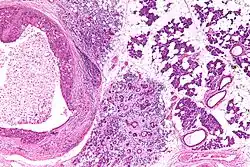

Their histologic appearance is similar to ductal breast carcinoma.

Intermed. mag. -